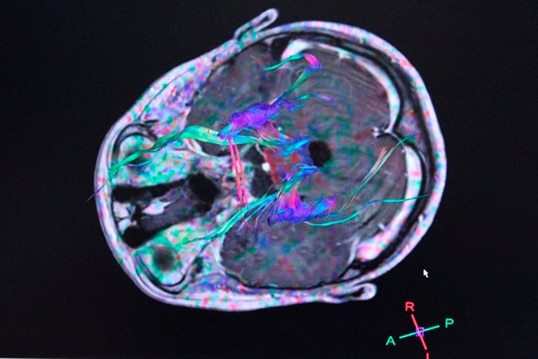

Sin embargo, el estudio liderado por Parnia sugiere que aún después de la muerte, se produce un impulso de energía en el cerebro. Y ello es lo que permite que los ‘fallecidos’ aún reciban información de su entorno.

Ya en el 2013, investigadores de la Universidad de Michigan observaron las señales eléctricas dentro de las cerebros de nueve ratas anestesiadas después de haber sido inducidas a un ataque cardiaco.

Poco después de la muerte clínica de los roedores, los investigadores observaron patrones de actividad en el cerebro relacionados con un estado de “hiper alerta”.

La ‘parte pensante’ del cerebro, el córtex cerebral también baja su actividad de manera instantánea, lo que significa que no se producen ondas cerebrales unos 20 segundos, según lo que se observa en un monitor.

Esta primera reacción inicia una cadena de procesos celulares que resultan en la muerte cerebral. Sin embargo, según el Dr. Parnia, “hasta que esto sucede, pueden pasar horas desde que el corazón deja de funcionar”.